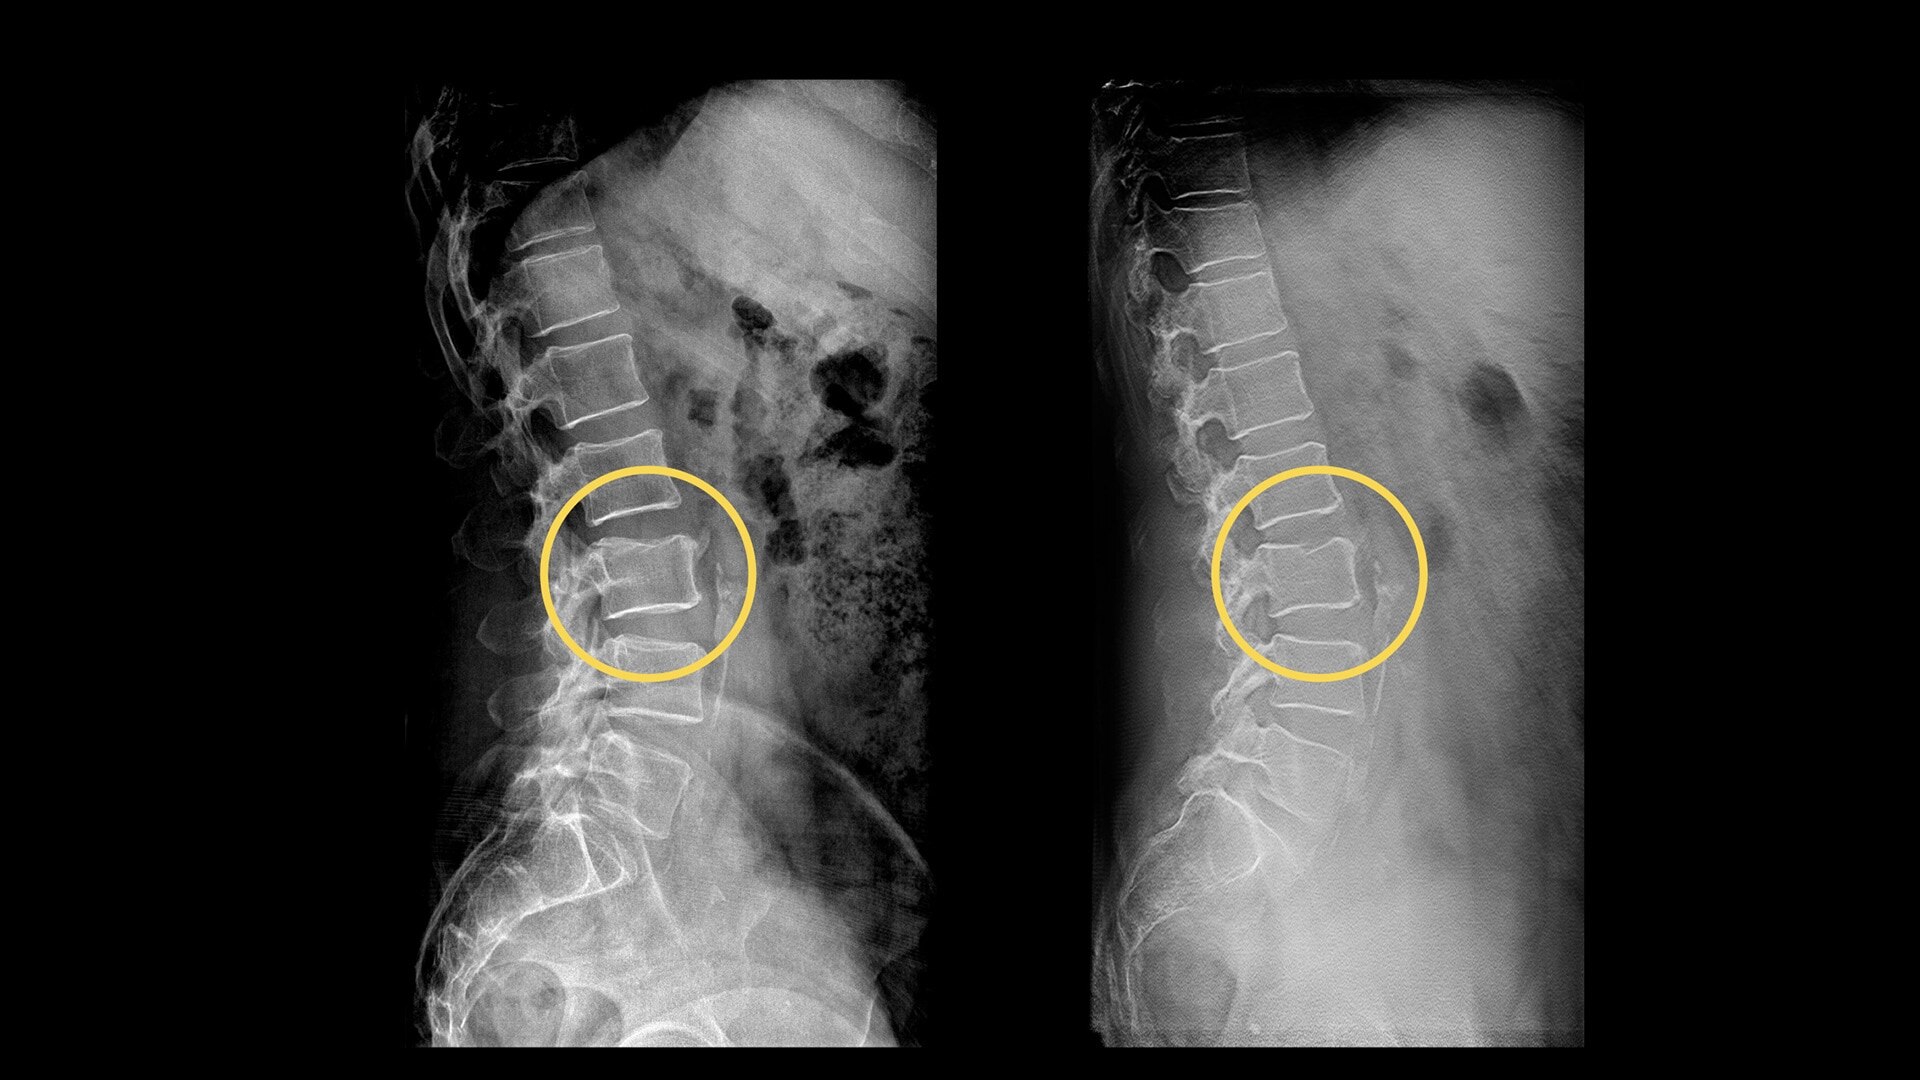

A fast and accurate alternative

Your department relies on standard radiography as the first diagnostic test for most chest, orthopedic and trauma cases. But hairline fractures or non-displaced fractures are difficult to detect on conventional X-rays.13 According to a recent study, 33% of scaphoid fractures are missed on the first X-ray.14

Digital tomosynthesis can help you reduce time-to-diagnosis, decrease department costs and improve patient outcomes.